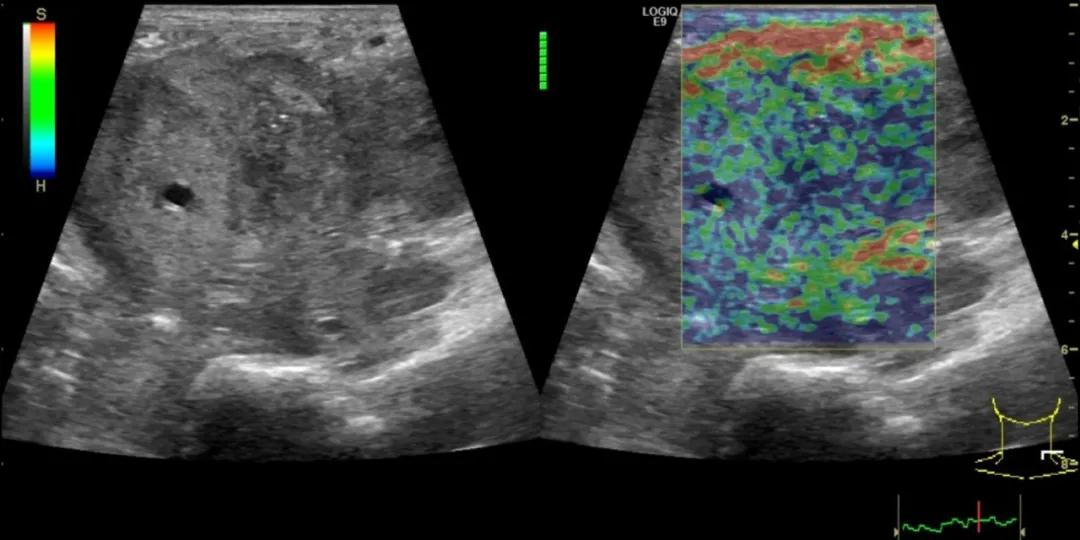

第三例是甲状腺癌患者,双侧甲状腺癌切除术后、碘治疗后一年余效果欠佳,超声显示左颈3区3枚低回声结节,穿刺示甲状腺乳头状癌转移。患者不愿意手术,希望采取局部治疗。对病灶进行液体隔离后采取热消融术,由于淋巴结较小,热消融一分钟左右完全灭活,术后增强影像显示没有脏器充填。

(病例3图例)